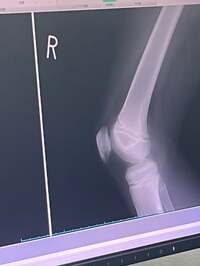

この日、ユカイは「膝が痛いと言う頼音」と頼音くんが膝の痛みを訴えたことを明かし「サッカーの練習は休みを取っていつもお世話になっている清水先生の所へ直行」と説明。「診断の結果はジャンパー膝」と診察を受ける頼音くんの姿を公開し「小学六年生成長期に伴うオスグッドなんて症状もあるから大事にいこう」と呼びかけた。